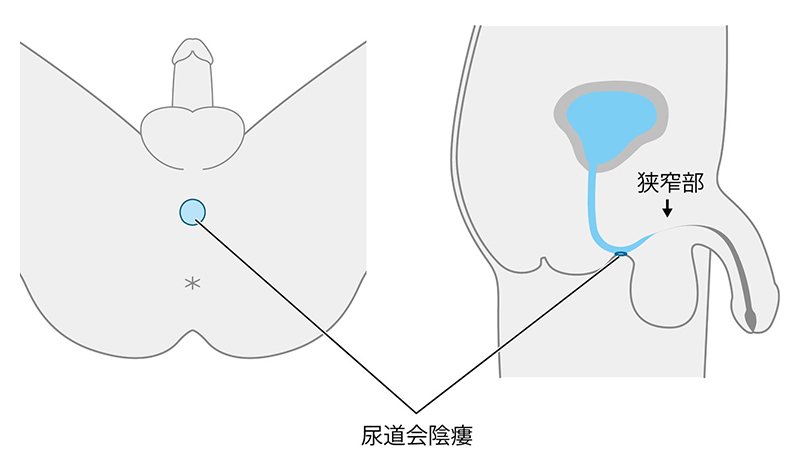

尿道狭窄症とは 堀口明男 Official Site

尿道狭窄症とは 堀口明男 Official Site

尿道形成術とは 堀口明男 Official Site